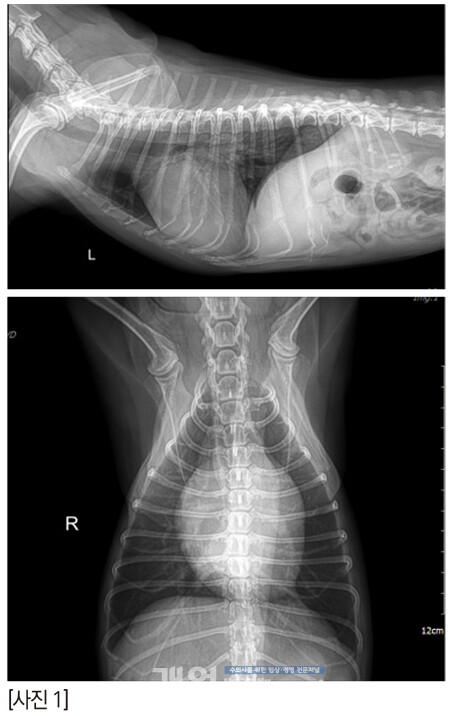

짱아의 방사선은 이렇다. 오랫동안 MMVD B2 로 유지되고 있다.

콩팥에는 결석이 있고, 복부초음파에서 콩팥은 점점 나이가 들어가고 있는 것은 확실하다.

그렇다면 열 다섯살 반 짱아의 회복은 어땠을까?

수술 2시간 후의 짱아, 정말 대단하다!!!!! [사진 9] 잘 회복해서 3일차에 퇴원을 했지만 나이가 고령이어서 분명 크고 작은 문제들이 수술 2~3주 내에 지나갈 것 같았다.